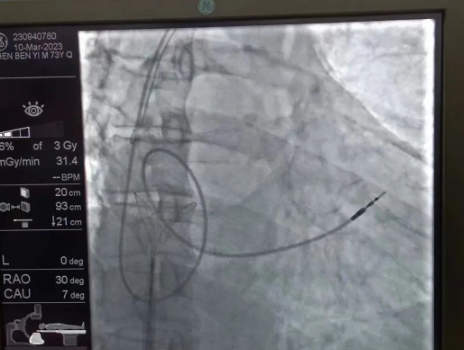

術(shù)中,孫書紅醫(yī)師首先切開起搏器囊袋,游離出起搏器脈沖發(fā)生器,發(fā)現(xiàn)起搏電極完全斷裂,連接于起搏脈沖發(fā)生器,殘端約10cm;考慮患者為起搏依賴患者,需再次植入新的起搏電極導(dǎo)線,穿刺了腋靜脈,放置導(dǎo)絲;同時,李偉杰教授穿刺了左、右股靜脈,于右股靜脈置入了”抓捕器”,左股靜脈備用臨時起搏通路,以防術(shù)中出現(xiàn)心跳驟停。為了準(zhǔn)確抓捕到心房內(nèi)的在逃起搏電極,李偉杰教授將導(dǎo)管室的X光機(jī)球管調(diào)整成了冠脈模式,這就意味著在抓捕過程中,醫(yī)生要比平時的手術(shù)“吃”更多射線……

在透視模式下,抓捕全憑醫(yī)生的經(jīng)驗(yàn)與手感,一次次嘗試,一次次失敗,在場外觀摩手術(shù)的醫(yī)生同樣為李偉杰教授捏了一把汗,“找到了!”電子屏里抓捕器向在逃起搏電極“發(fā)起進(jìn)攻”,一把逮住并順利拔出一根長達(dá)58cm的起搏電極。